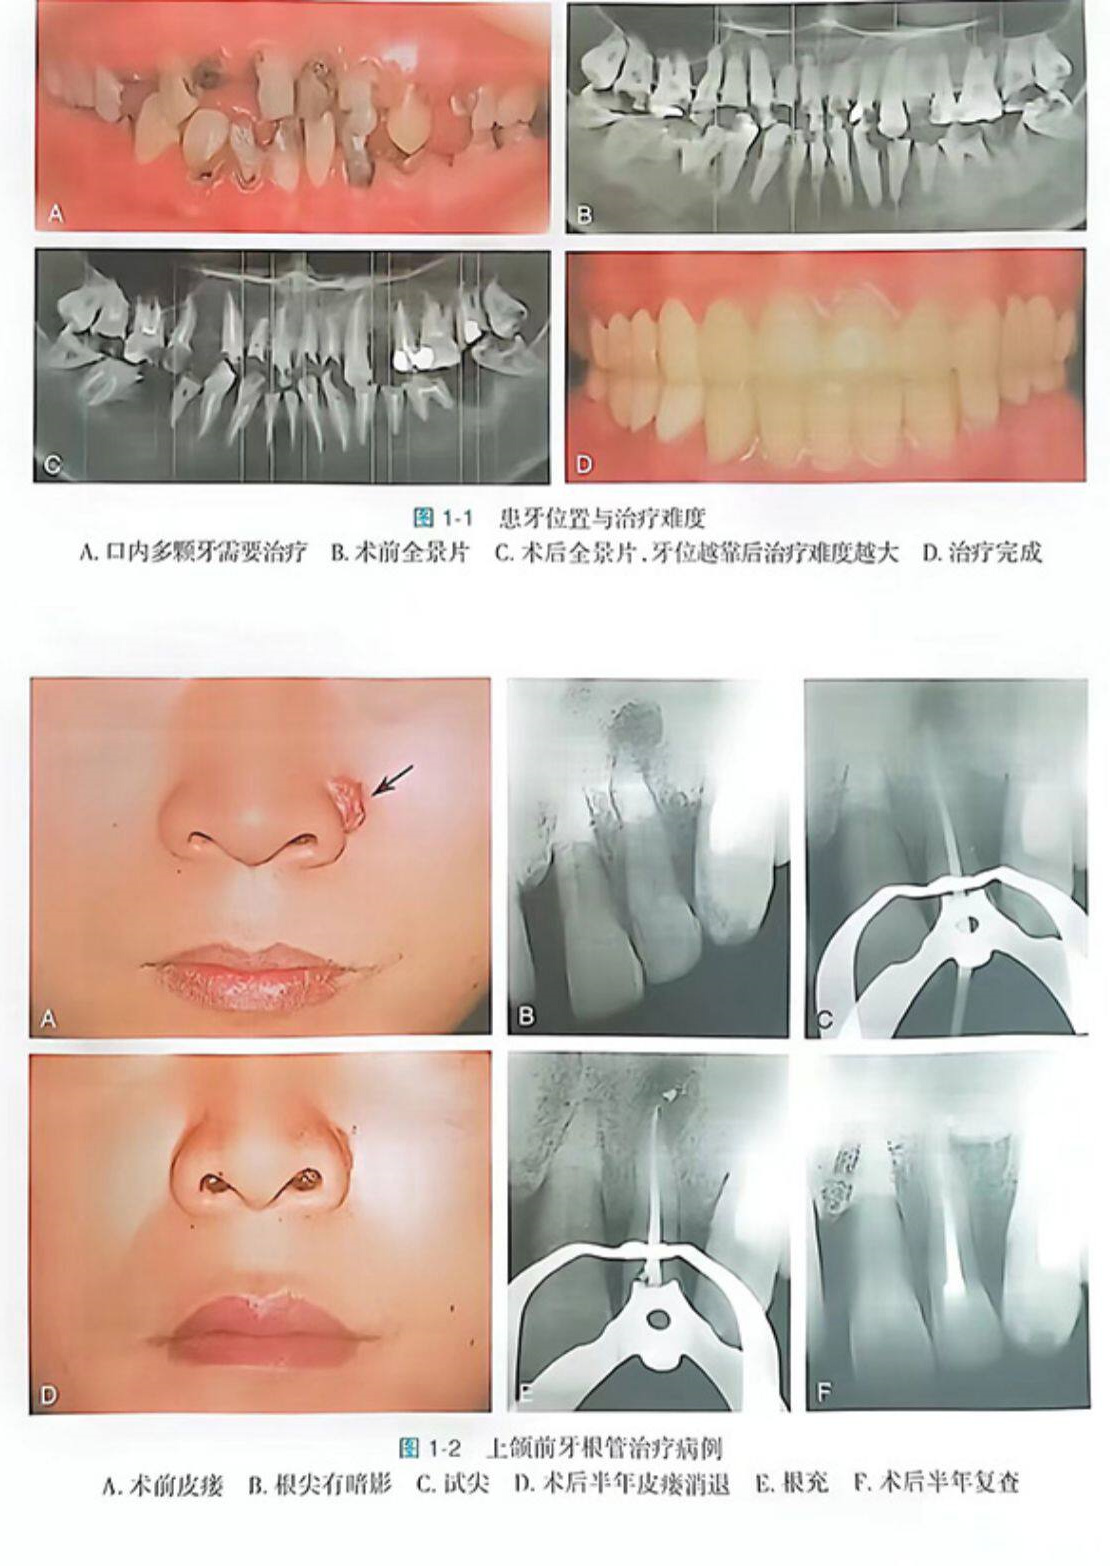

第一章病例选择

一、根管治疗的难易度